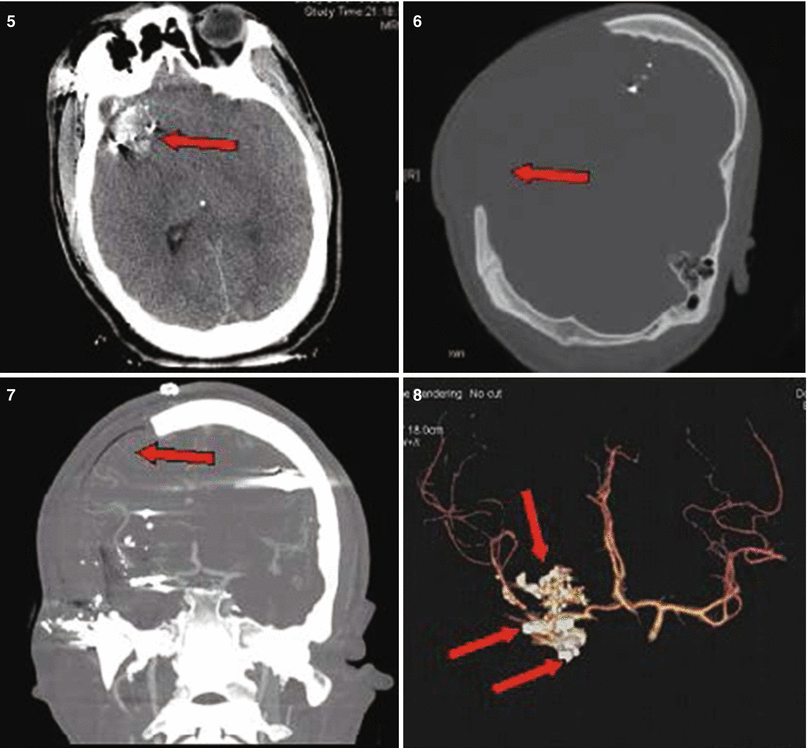

Fig. 27.3

Patient No. 3: a 30-year-old female, who sustained a solitary GSW to the back of her head from close range. Entry wound on the occiput and no exit wound. Arrow in plates 1 and 2 points at the retained bullet case. Arrow in plate 3 shows the bullet case as seen in the corresponding head CT on axial CT bone window. Arrows in plate 4 point at a dilated right lateral ventricle and at left perimesencephalic hemorrhage. Arrows in plate 5 show the enlarging hematoma in the CP angle and a hematoma in the left sided posterior fossa. Arrow in plate 6 shows the bilateralsuboccipital craniectomy site that was created to gain access for evacuation. Arrow in plate 7 points at the evatuation side of the previously seen hematoma in 5. Arrow in plate 8 points at the R frontal EVD catheter inserted to treat the occlusive hydrocephalus